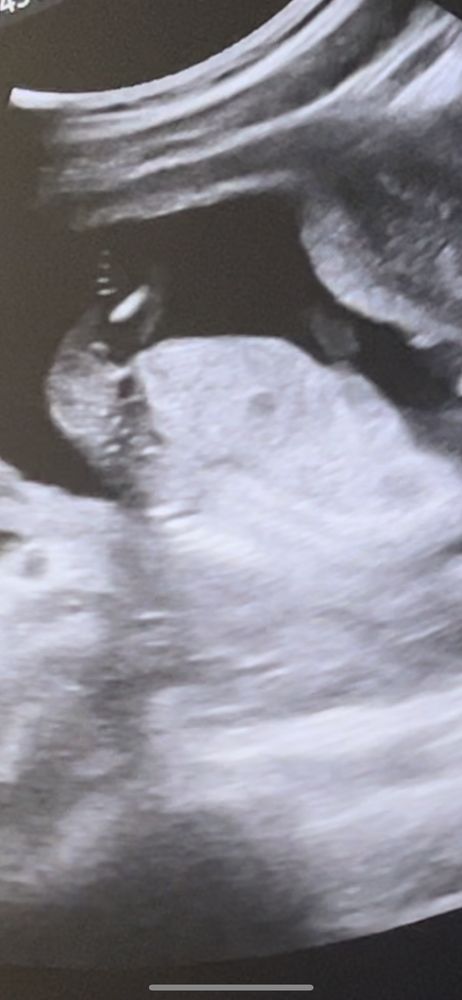

Пол 15 недель

На этом снимке я вообще не вижу бугорок (

Мне кажется мальчик 😅

Mamashka, Самое интересное, что врач говорит я ничего торчащего не увидела, когда я ей сказала, что мне показался перчик😅. Ну 25 декабря 2 скрининг, надеюсь не спрячется 😃 и на 1 скрининге сказали девочка скорее всего 😄

Виолетта, хотя знаете я присмотрелась, наверное все таки девочка, а отсвечивает может же и пуповина,поэтому показался перчик ахахаах

Eva , здравствуйте 😃 мальчик) Не зря я в 15 нед на узи увидела что-то. А Узист говорила признаков мальчика нет😅😅😅 Когда я сказала, что заметила торчок😀